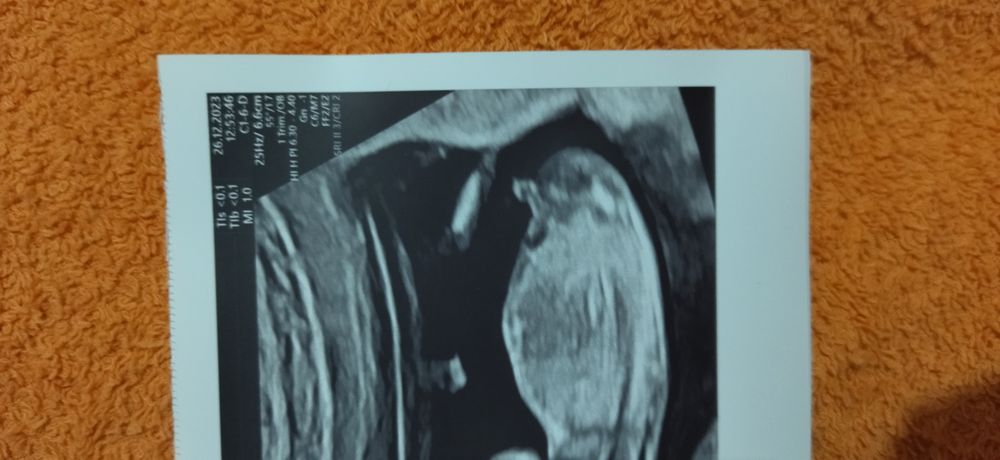

Судя по половому бугорку больше похоже, что это мальчик💙

Мне кажется мальчик)

Да я вам даю 150% что мальчик

Очень много ошибок бывает на таком сроке. На втором скрининге будет лучше видно.

На парня похоже🙏Главное здоровенький🌸